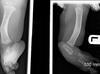

NF1 infant with these findings needs what additional work up?

Bracing and referral to genetic to evaluate for systemic disease The radiographs show a severe pseudarthrosis tibia/fibula that has fractured. This is highly associated with neurofibromatosis type I, which needs to be evaluated with a genetics workup before discussing treatment. Cast immobilization is not needed if the child is not walking and not in pain. Surgical management should proceed only after the workup is complete ## Footnote NF is commonly associated with the following orthopedic manifestations: anterolateral tibial bowing, pseudoarthrosis of the tibia, pseudoarthrosis of the forearm, hemihypertrophy, scoliosis, and atlantoaxial instability. Characteristics of forearm pseudoarthrosis consist of outward deformity, little outward signs of trauma, the disappearance of the medullary canal in the distal third of the forearm, and bowing deformity. Congenital forearm pseudoarthrosis is associated with NF in approximately 50% of cases.